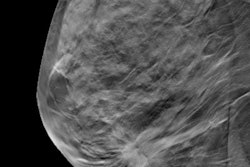

General radiologists and breast imaging subspecialists can both benefit significantly from reading digital breast tomosynthesis (DBT) studies concurrently with artificial intelligence (AI) software, reported researchers from the University of Pennsylvania and computer-aided detection (CAD) firm iCAD.

In a study involving more than 20 readers, the researchers found that concurrent use of AI during image interpretations resulted in better diagnostic performance for general radiologists and breast imaging subspecialists, with the general radiologists achieving the largest gains. What's more, reading times were cut approximately in half for both groups of radiologists.

To assess the outcomes from concurrent use of AI with DBT separately for breast subspecialists and general radiologists, the researchers conducted a multireader, multicase study involving 24 readers and 260 DBT cases. The readers included 13 breast imaging subspecialists who devoted 75% or more of their time to breast imaging, as well as 11 general radiologists who spent less than 75% of their time reading breast imaging exams. All, however, had interpreted more than 500 DBT exams in the last two years.

Of the DBT cases, 65 were biopsy-proven as cancer and 65 were biopsy-proven as benign. The radiologists -- who had a range of experience from one to 34 years in clinical practice -- read each exam with and without AI, with at least four weeks in between reading the same case, according to the researchers. The interpretation order was randomized, and the radiologists were blinded to the patient's history and prior images. Reading time was calculated from the time the reader began reviewing images to the time the reader determined if the case had any suspicious lesions.

Developed by iCAD, the deep learning-based software used in the study detects both soft tissue and calcific lesions on DBT slices, Hoffmeister said. It also provides "certainty of finding" scores on both a lesion and case level.